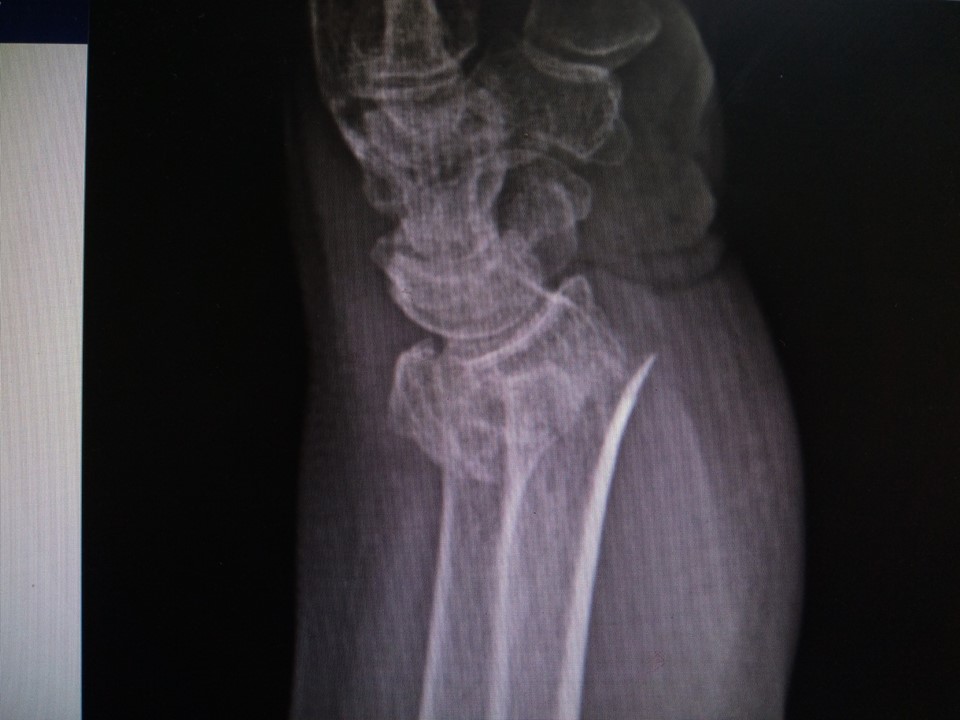

Al evaluar su muñeca izquierda pude notar que tenia mucho aumento de volumen y apenas la toque el dolor se noto inmediatamente con un enorme grito que casi me deja sordo, por lo cual le dije a la residente que la llevara a hacer unas radiografías de esa muñeca que lucía algo fea.

Al ver las radiografías enseguida se hizo notar una horrible fractura de la porción mas distal del radio izquierdo, en vista de los hallazgos no había más opción que levarla a quirófano para reducir la fractura.

Y así mismo sucedió, la señora Cecilia subió a quirófano y una hora después yo con mi equipo subimos a realizar la cirugía más fea del día, donde pudimos realizar la reducción de la fractura y la estabilizamos con un tutor externo para muñeca, lo cual consiste en una serie de clavos, tuercas, rotulas y barras.